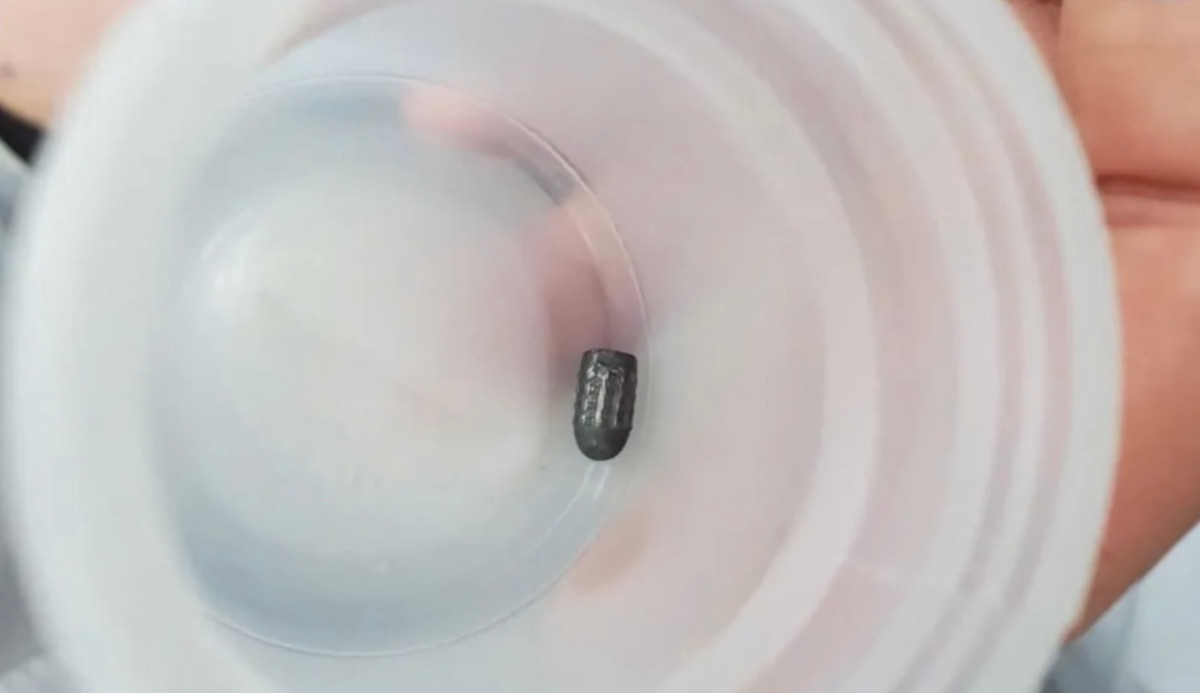

Ca mổ kéo dài 45 phút, các bác sĩ mở rộng vết thương khoảng 3cm và lấy ra dị vật kim loại hình đầu đạn, kích thước 0,5x0,3cm. Đầu đạn xuyên qua lớp da, chạm nhẹ xương chẩm, không gây tổn thương nghiêm trọng đến não hay các cấu trúc lân cận. Hiện bệnh nhân tỉnh táo, tiếp xúc tốt, vết mổ khô, không có dấu hiệu thần kinh bất thường.